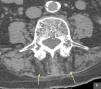

Varón de 86 años, independiente para las actividades de la vida diaria, con antecedentes patológicos de cardiopatía isquémica, fibrilación auricular crónica, diabetes mellitus tipo I e hipotiroidismo. Consultó por dolor lumbar de características mecánicas e inestabilidad de la marcha, sin antecedente traumático previo. Se acompañaba de una cifosis armónica progresiva, reducible con la bipedestación y el decúbito. En la exploración física destacaba el aumento de la curvatura anteroposterior del raquis que condicionaba el contacto de las costillas con la pelvis y que se reducía con el decúbito (fig. 1), ligera flexión de las rodillas y retroversión de la pelvis. El resto de la exploración física resultó anodina. Se realizó radiografías de columna dorsal y lumbar (anteroposterior y perfil) que no mostraron alteraciones significativas a excepción de signos degenerativos. Con la sospecha diagnóstica de camptocormia, se solicitó una tomografía computarizada de columna lumbar donde se observó una atrofia muscular selectiva paravertebral posterior (fig. 2), compatible con la orientación diagnóstica inicial. Se inició tratamiento analgésico y rehabilitación.

El diagnóstico es clínico, apoyado por las pruebas complementarias, como la tomografía computarizada de la columna dorso lumbar donde se observa hipodensidad y atrofia de los músculos paravertebrales que se interpreta como una involución de la grasa. Teniendo en cuenta la etiología heterogénea de este trastorno, se realizarán otras exploraciones como un electromiograma; estudio hormonal, del metabolismo óseo y de enzimas musculares; tomografía computarizada craneal y/o resonancia para estudio de ganglios basales que pueden estar afectados en pacientes con enfermedad de Parkinson y camptocormia1 o incluso biopsia muscular.